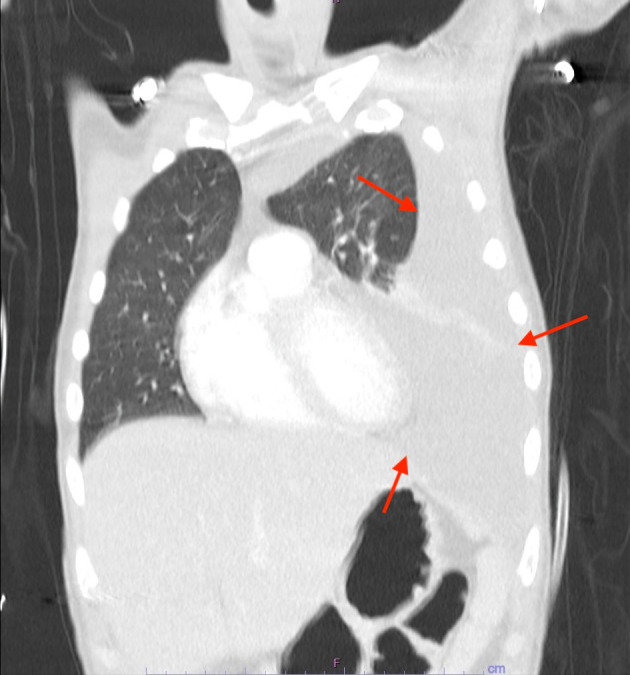

原发性积液性淋巴瘤(PEL)是一种罕见的、侵袭性的大b细胞淋巴瘤变体,它总是与人类疱疹病毒8 (HHV8)相关,主要发生在人类免疫缺陷病毒(HIV)感染的患者中,其致瘤性通常因同时感染eb病毒而增强。它通常表现为体腔内的浆液积液,没有可检测到的实体瘤。PEL的腔外变异可能是一个诊断挑战。一名37岁男性HIV/ AIDS患者被转至我院接受纵隔肿块检查,诊断为嗜血球性淋巴组织细胞增多症(HLH)、发热、全血细胞减少症、肝脾肿大、腹膜后淋巴结病和耗损综合征。增强计算机断层扫描显示一大块软组织肿块沿中/后纵隔延伸至左肺门,左侧胸腔积液大量。内镜下细针活检显示大的多形性淋巴瘤细胞片,核仁突出,细胞质丰富。这些细胞在胸膜液细胞自旋涂片上也可见。免疫组化染色显示淋巴瘤细胞CD3(小亚群)、CD45、CD138、MUM-1和HHV8阳性,CD5、CD20、CD30、ALK1、AE1/3和PAX-5阴性。淋巴瘤细胞eb病毒编码RNA(原位杂交)也呈阳性。腔外PEL中的实性肿块已被证明累及淋巴结和/或实体器官,如胃肠道、肺、肝、脾和皮肤,其表型与典型PEL相似,只是它们可能表达CD45表达较低的b细胞标记物和/或t细胞抗原的异常共表达。本病例显示了不同寻常的PEL表现为纵隔肿块伴HLH。

Primary effusion lymphoma (PEL) is a rare, aggressive large B-cell lymphoma variant that is invariably associated with human herpesvirus 8 (HHV8), predominantly in human immunodeficiency virus (HIV)-infected patients, and its oncogenicity is often augmented by coinfection with Epstein-Barr virus. It typically presents as a serous effusion in body cavities without detectable solid tumors. The extracavitary variant of PEL may represent a diagnostic challenge. A 37-year-old man with HIV/acquired immunodeficiency syndrome (AIDS) was transferred to our hospital for evaluation of a mediastinal mass with associated clinically diagnosed hemophagocytic lymphohistiocytosis (HLH), fever, pancytopenia, hepatosplenomegaly, retroperitoneal lymphadenopathy, and wasting syndrome. Contrast-enhanced computed tomography showed a large soft tissue mass extending along the middle/posterior mediastinum into the left hilum and a large left pleural effusion. Endoscopic fine-needle biopsy of the lesion showed sheets of large pleomorphic lymphoma cells with prominent nucleoli and abundant cytoplasm. These cells were also seen on the cytospin smear of pleural fluid. Immunohistochemical stains showed lymphoma cells positive for CD3 (small subset), CD45, CD138, MUM-1, and HHV8 and negative for CD5, CD20, CD30, ALK1, AE1/3, and PAX-5. The lymphoma cells were also positive for Epstein-Barr virus-encoded RNA (EBER) (in situ hybridization). Solid masses in extracavitary PEL have been shown to involve lymph nodes and/or solid organs such as the gastrointestinal tract, lung, liver, spleen, and skin, with a similar phenotype as classic PEL except that they may express B-cell markers with lower expression of CD45 and/or aberrant coexpression of T-cell antigens. This case illustrates the unusual manifestation of PEL as a mediastinal mass with associated HLH.